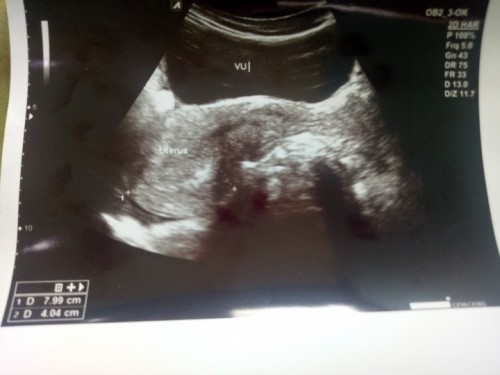

Usg

Bisa tolng bacakan gak artinya apa

GA atau Usia Kehamilan Istilah GA yang tertera dalam foto USG adalah Gestational Age, Ma. GA menunjukkan perkiraan umur kehamilan mama yang berdasarkan berdasarkan panjang tungkai kaki, tungkai lengan, diameter kepala, hingga perkembangan organ tubuh janin. CRL atau Crown Rump Length CRL atau Crown Rump Length menunjukkan keterangan yang menunjukkan ukuran jarak dari ujung kepala hingga ujung kaki janin. Biasanya, CRL digunakan dokter untuk mengukur janin di kehamilan trimester awal. GS atau Kantung Kehamilan GS atau Gestational Sac merupakan ukuran kantung kehamilan yang menganggap dengan bulatan hitam. GS umumnya muncul pada hasil foto USG trimester awal. Diameter BPD atau Biparietal BPD atau Diameter Biparietal menunjukkan ukuran tulang pelipis kiri dan kanan, Ma. BPD umum digunakan untuk mengukur janin saat trimester dua atau tiga. AC atau Abdominal Circumferencial AC atau Abdominal Circumferencial merupakan perkiraan ukuran lingkar perut janin. Nah, gabungan AC dengan BPD maka hasilnya akan berupa perkiraan berat janin dalam kandungan. HC atau Head Circumferencial HC atau Head Circumferencial merupakan keterangan terkait ukuran lingkaran kepala janin dalam kandungan. FL atau Femur Length Sementara untuk FL atau Femur Length merupakan keterangan yang berkaitan dengan ukuran panjang tulang paha janin. FW atau Fetal Weight FW atau Fetal Weight merupakan keterangan mengenai berat janin dalam kandungan. FHR atau Denyut Jantung Janin Sementara untuk DJJ atau Denyut Jantung Janin menunjukkan frekuensi detak jantung janin. LMP atau Last Menstrual Period LMP atau Last Menstrual Period merupakan hitungan hari pertama haid terakhir. Digunakan sebagai acuan acuan umur janin dalam kandungan. EDD atau Estimated Delivery Date EDD atau Estimated Delivery Date berdasarkan perkiraan mengenai perkiraan persalinan berdasarkan tanggal menstruasi. Mama mungkin lebih akrab dengan istilah HPL (Hari Perkiraan Lahir) dibandingkan istilah EDD.